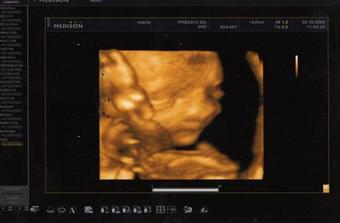

20.7. Prediko Zlín, screeining v 1.trimestru- vše OK,miminka s sebou mrskala jak splašená 🙂, no hold celý tatínek.....

10.9. 2009- 2. screening Prediko Zlín -oprava 11.9.-jsem popleta- vše ok- čekáme 2 chlapečky Bořka a Bruna....za 3 tt kontrola v Prediku- oba chlapečci jsou zdraví a šikovní.......